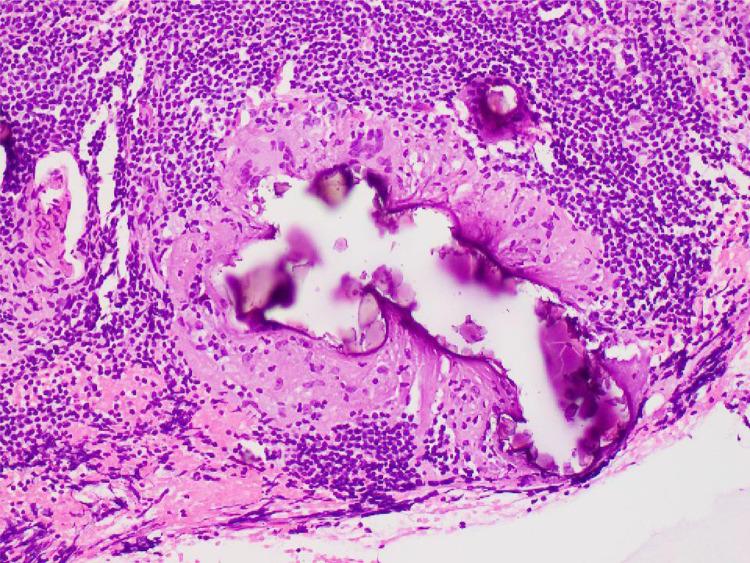

A 48-year woman was found to have bilateral axillary nodal microcalcifications on screening mammogram; a new finding compared to the prior mammogram done about 8 years ago. Combining the new finding with the amorphous and fine morphology of the microcalcifications, deemed it suspicious. In the absence of a definite benign cause, that could be attributed to this finding, biopsy was performed. Histology from the bilateral axillary node was reported to be benign with calcifications identified within granulomas. There are only a few cases with bilateral axillary nodal microcalcifications reported in the literature till date. Most of these are from ovarian cancer or related to chrysotherapy for rheumatoid arthritis. Our case is distinct from them as this rare finding was not due to any of the known etiologies and the morphology is quite different from the known granulomatous causes. As we report this rare case, we also revisit the causes of axillary nodal microcalcifications. Familiarity with this subject can help the reporting radiologists to avert an invasive procedure like biopsy in some cases, if the cause of benignity can be confidently identified.

一名48岁女性在乳腺筛查钼靶检查中发现双侧腋窝淋巴结微钙化;与约8年前进行的前一次钼靶检查相比,这是一个新发现。结合微钙化的无定形和细颗粒形态,该发现被视为可疑。由于没有明确的良性病因可归因于此发现,因此进行了活检。双侧腋窝淋巴结的组织学报告为良性,在肉芽肿内发现钙化。迄今为止,文献中仅报道了少数双侧腋窝淋巴结微钙化病例。其中大多数来自卵巢癌或与类风湿性关节炎的金疗法有关。我们的病例与它们不同,因为这一罕见发现并非由任何已知病因引起,且形态与已知的肉芽肿病因有很大差异。在报告这一罕见病例时,我们也重新审视了腋窝淋巴结微钙化的病因。熟悉这一主题有助于报告放射科医生在某些情况下,如果能够确定良性病因,避免进行活检等侵入性检查。